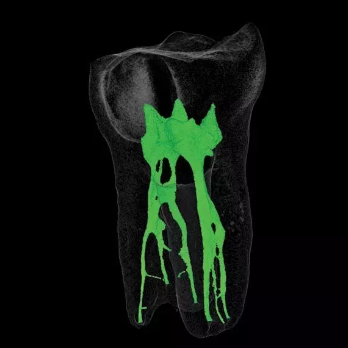

根管侧支

牙根管系统详解